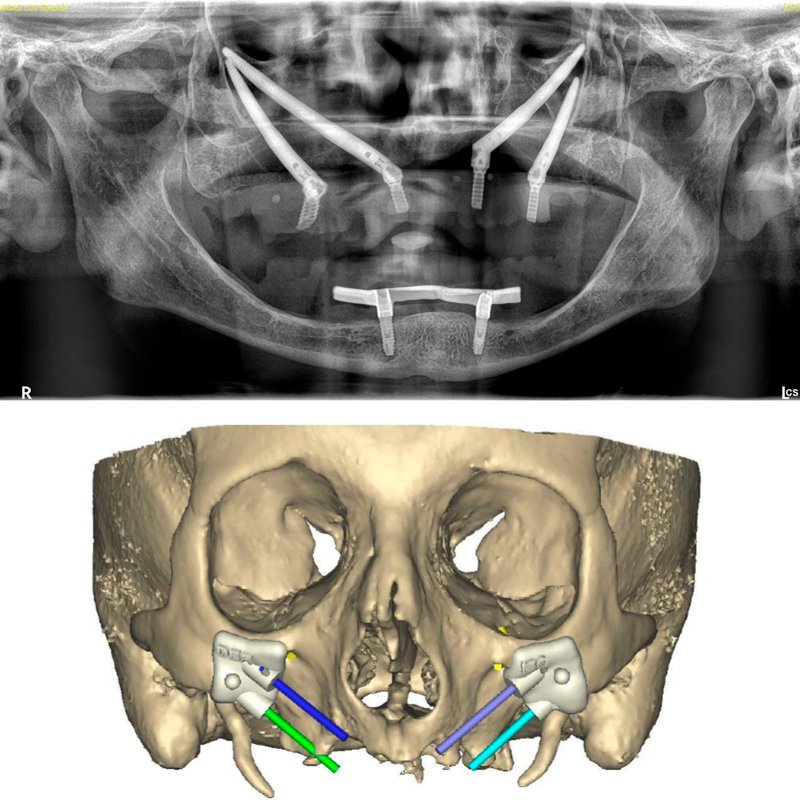

Decidí recuperar mi sonrisa y fui a la clínica dental donde me atendió la Dra. Laura Zárate. Me explico paso a paso como sería el procedimiento. Resolvió todas mis dudas y me dio la confianza para iniciar el tratamiento.